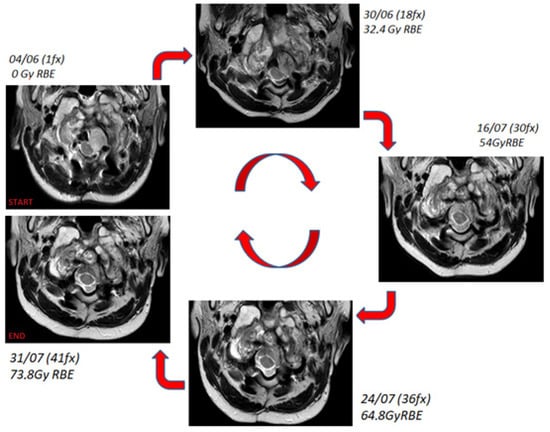

Four MRI examinations (T2-weighted sequence, without contrast) were acquired over the treatment course at doses of 32.4, 54, 64.8, and 73.8 GyRBE, respectively (Figure 4).

The figure shows temporal sequence of T2-weighted MR axial images of the nodular component at different times. The upper-left image represents the situation at diagnosis, while the others (clockwise direction) show the evolution during the treatment.

The bony component of the lesion around the tooth of the axis did not change in volume or morphology over the course of treatment, whereas the nodule component showed a progressive dimensional modification from 2.323 cc at the beginning of the treatment to 2.829 cc at 32.4 Gy RBE, 2.051 cc at 54 Gy RBE, and 1.045 cc at 64.8 Gy RBE and 73.4 Gy RBE (Figure 5). This led to a total reduction from the beginning to the end of proton therapy of 1.278 cc (about 55% of the initial volume). This reduction allowed the decompression of the spinal cord.

The early response of this nodular component of chordoma was an unexpected finding during the irradiation, which should be described as an early therapeutic response. Such a result is even more meaningful considering that this tumor area received less than prescribed dose because of its proximity to the spinal cord. At the same time, although the dose to the spinal cord was constrained to 54 GyRBE, thanks to the quality of the treatment plan, at least 50% of this tumor area received 70 GyRBE. This may justify the good radiological outcome.

The irradiation with proton therapy at high dose levels in a child with such a lesion was not trivial. Taking into account the critical OARs like the cervical chord, bulb-cervical chord junction, brainstem in close proximity to the tumor, and the dose gradient required to cover the target on one hand while sparing the OARs on the other hand makes this kind of treatment very challenging. The radiological monitoring, due to the unexpected early response of the nodular component, allowed us to check that the irradiation took place in a safe manner without damaging the critical structures. Despite the dimensional changes in the nodular components adjacent to the bulb-cervical cord junction, the margin adopted for planning proved to be adequate, so no adaptive re-planning was performed.

Figure 4. Treatment monitoring over the proton therapy course with T2-weighted MRI.